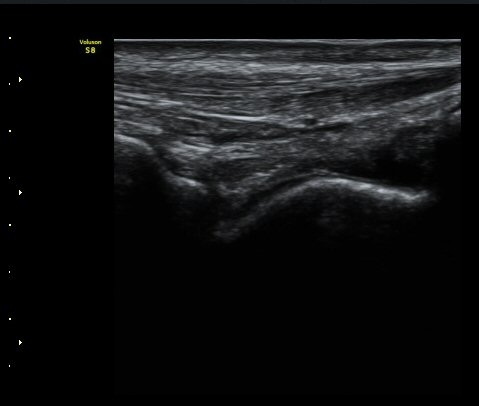

Àü°Å°ñºñ°ñÀδë Á¾´Ü¸é°Ë»ç¿¡¼­ ÀδëÀÇ ÀüÃþÆÄ¿­°ú ºÎÁ¾ÀÌ °üÂûµÈ´Ù(±×¸² 3, 4).

°ÇÃø(±×¸² 5)°ú ºñ±³ÇØ º¸¸é È¯ÃøÀÇ ÀÎ´ë ¼Õ»óÀÌ ¶Ñ·ÈÇÏ´Ù.